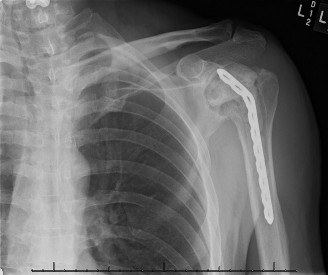

The correct answer is (E). Given that her rotator cuff has atrophied and has fatty infiltration to the point where there are equal parts fat and muscle, this is considered an irreparable rotator cuff tear. Repair should not be attempted because of poor outcomes following repair (see last two paragraphs of this discussion below). A reverse total shoulder arthroplasty is an alternative to repair that should be used in cases of massive, irreparable rotator cuff tears. It is a semi-constrained prosthesis that restores function in patients with massive rotator cuff tears by constraining a concave humeral cap inferior to a semispherical glenoid component (glenosphere). This creates an inferior force-couple and a fulcrum that replaces the stabilizing function of the infraspinatus maintaining a center of rotation around which the shoulder can move. This allows the deltoid to abduct and flex the shoulder without causing the humerus to migrate superiorly and about the acromion. In an elderly patient with a massive, irreparable rotator cuff tear (as in this patient), a reverse total shoulder arthroplasty is the procedure of choice.

It should be noted that reverse total shoulder arthroplasty is also the procedure of choice in patients with cuff-tear arthropathy (aka rotator cuff arthropathy). Characteristics of cuff-tear arthropathy include superior migration of the humerus due to a massive rotator cuff tear, glenohumeral joint destruction, subchondral osteoporosis, and humeral head collapse (see Fig. 2–17). A reverse total shoulder

arthroplasty in this case serves the purpose of eliminating pain caused by glenohumeral joint arthritis while restoring functional motion and is the procedure of choice in patients with cuff-tear arthropathy.

Figure 2–17_X-rays of a patient showing evidence of cuff tear arthropathy. The humerus is migrated superiorly, the glenohumeral joint is destroyed, there is subchondral osteoporosis, and the humeral head is collapsed. (From Ecklund KJ, Lee TQ, Tibone J, Gupta R. Rotator cuff tear arthropathy. _J Am Acad Orthop Surg. 2007;15(6):340–349.)

A hemiarthroplasty (Answer A) was previously the procedure of choice for cuff-tear arthropathy until the reverse total shoulder prosthesis was developed. A hemiarthroplasty reliably relieves pain, but it does not restore function as well as the reverse total shoulder. Also, if the patient had a previous coracoacromial ligament release or anterior deltoid detachment, they are at risk for anterosuperior escape of the humeral head after hemiarthroplasty.

A total shoulder arthroplasty (Answer B) is contraindicated in the case of cuff-tear arthropathy because of glenoid component loosening. If a glenoid component is used in this patient, the superior translation of the humeral head component on the glenoid component could cause it to loosen and rock, producing a “rocking-horse” glenoid component.